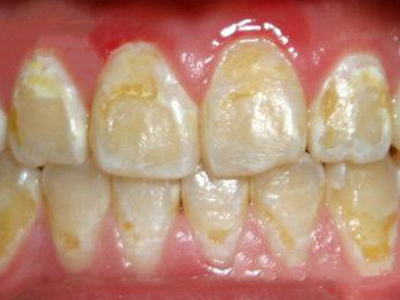

酸蚀症牙齿有大量黄斑及白斑图

患酸蚀症时,牙齿表面可出现大量黄斑及白斑,交错分布,形状不规则,境界不清楚,牙面还有少量竖行裂纹,是牙骨质受破坏的表现,需积极防控致病因素。